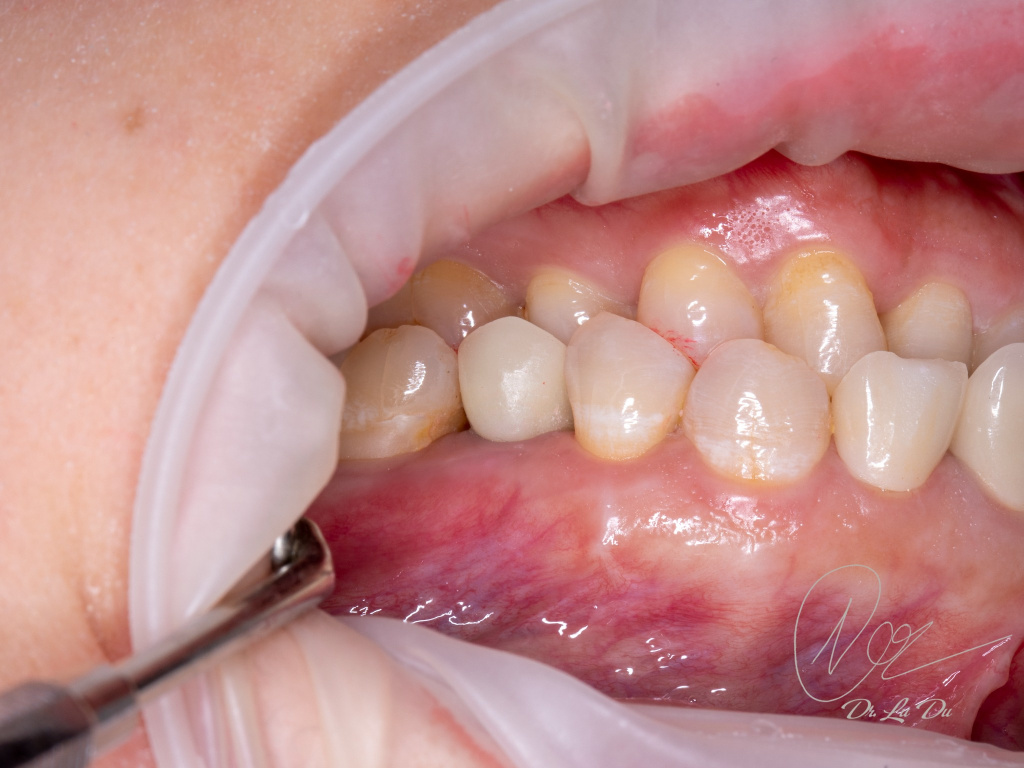

Имплантация AnyRidge с двусторонним закрытым синус-лифтингом.

Осложнения: правосторонний гайморит.

Кейс MINEC: Dr Lu Du